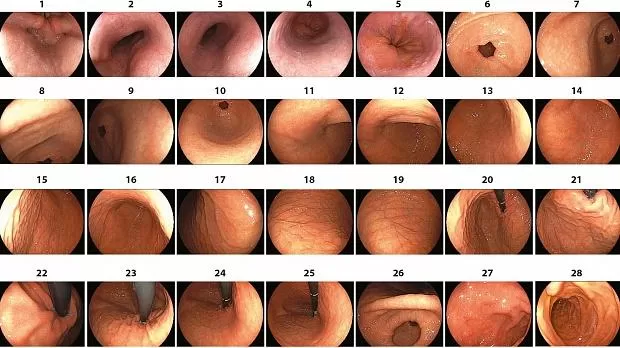

В последнее время фотодокументация стала полезным инструментом для измерения качества при эндоскопии, а фотографии ориентиров слепой кишки - как индикатор полноты колоноскопии. 8 В связи с этим Европейское общество эндоскопии желудочно-кишечного тракта (ESGE) заявило, что фотодокументация всех анатомических ориентиров во время эндоскопии верхних отделов ЖКТ может считаться показателем полного обследования. 4 Основываясь на этом соображении, а также на принципах внутрипросветной анатомии и признанных ориентиров, было описано в общей сложности 28 уникальных внутрипросветных областей, составляющих всю внутреннюю выстилку верхнего отдела желудочно-кишечного тракта, от гипофаринкса до второй части двенадцатиперстной кишки. 3 , 9Фоторегистрация этого каркаса слизистой оболочки является основой для получения полной фотодокументации. Таким образом, этот последовательный перекрывающийся реестр может представлять собой надежный индикатор полноты. 3 Тем не менее, практического руководства для тщательного фотодокументирования этого каркаса слизистой оболочки никогда не было.

В 2018 году было диагностировано более 1000000 новых случаев рака желудка, и он остается пятым по частоте диагностирования рака в мире. 17 В дополнение к легко узнаваемым ориентирам, таким как пилорический канал и угловая вырезка, есть и другие внутрипросветные ориентиры, которые, будучи однажды идентифицированными, являются ключевыми для достижения полного обследования. Эти ориентиры включают эпителиальную переходную зону на большей кривизне нижней трети; желудочная шпора, внешнее сдавливание задней стенки средней трети; свод - кармановидная верхняя часть верхней части тела; и кардия - отверстие, образующее в ретрофлексном виде соединение между пищеводом и желудком. 2Идентификация этих ориентиров вместе с передней и задней стенками, малой и большой кривизной, а также сечениями желудка 18 составляет основание для светового разделения желудка на пять больших областей: пилорический канал и антральный отдел; нижняя, средняя и верхняя трети; и меньшая кривизна, которые в общей сложности включают 21 область 2 , 3 , 9 (Таблица 1 ).

Данное заявление о позиции WEO представляет собой руководство по полной фотодокументации слизистой оболочки верхних отделов желудочно-кишечного тракта, выполняющее высококачественные рекомендации, установленные крупными эндоскопическими организациями в отношении полного наблюдения за слизистой оболочкой и соответствующей документации. 4 , 5 Это обследование, также известное как систематическая эндоскопия с буквенно-цифровым кодированием (SACE), облегчает полное обследование путем фотодокументирования 28 уникальных областей, от гипофаринкса до второй части двенадцатиперстной кишки. 2 , 3 , 9 Для обеспечения полноты, области, которые должны быть зарегистрированы, пронумерованы от 1 до 28, предоставляя экзаменаторам последовательность процедуры (видео S1 ).